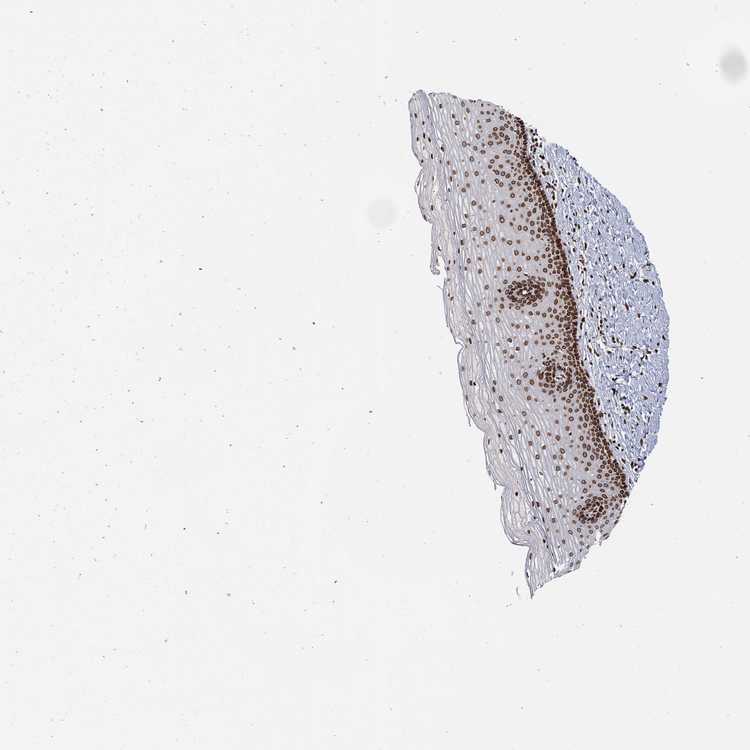

CERVIX - Antibody stainingi

Antibody staining in the annotated cell types in the current human tissue is reported as not detected, low, medium, or high, based on conventional immunohistochemistry profiling in selected tissues. This score is based on the combination of the staining intensity and fraction of stained cells.

Each image is clickable and will lead to virtual microscopy that enables deeper exploration of all samples and also displays staining intensity scores, fraction scores and subcellular localization as well as patient and tissue information for each sample.

Antibody CAB014895

Squamous epithelial cells High